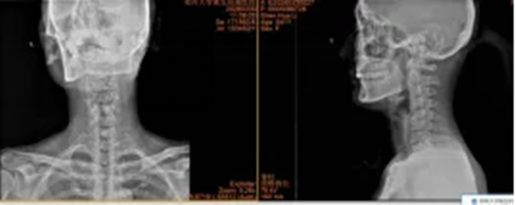

2.山西省晋城市沁水县龙港镇 44岁李女士

640 (2)_副本